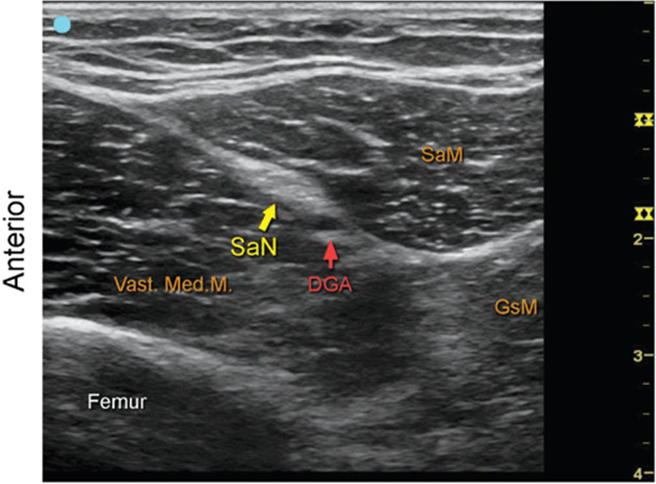

Saphenous Nerve at Distal Thigh

FIGURE 7.53.2A Ultrasound transducer position to image the saphenous nerve at distal thigh.

FIGURE 7.53.2B Ultrasound image of the saphenous nerve at distal thigh.

FIGURE 7.53.2C Labeled Ultrasound image of the saphenous nerve at distal thigh.

FIGURE 7.53.2D Labeled cross-sectional anatomy of the saphenous nerve at distal thigh.

Abbreviations: SaN, Sartorius Nerve; DGA, Descending Genicular Artery; SaM, Sartorius Muscle; GsM, Gracilis Muscle.